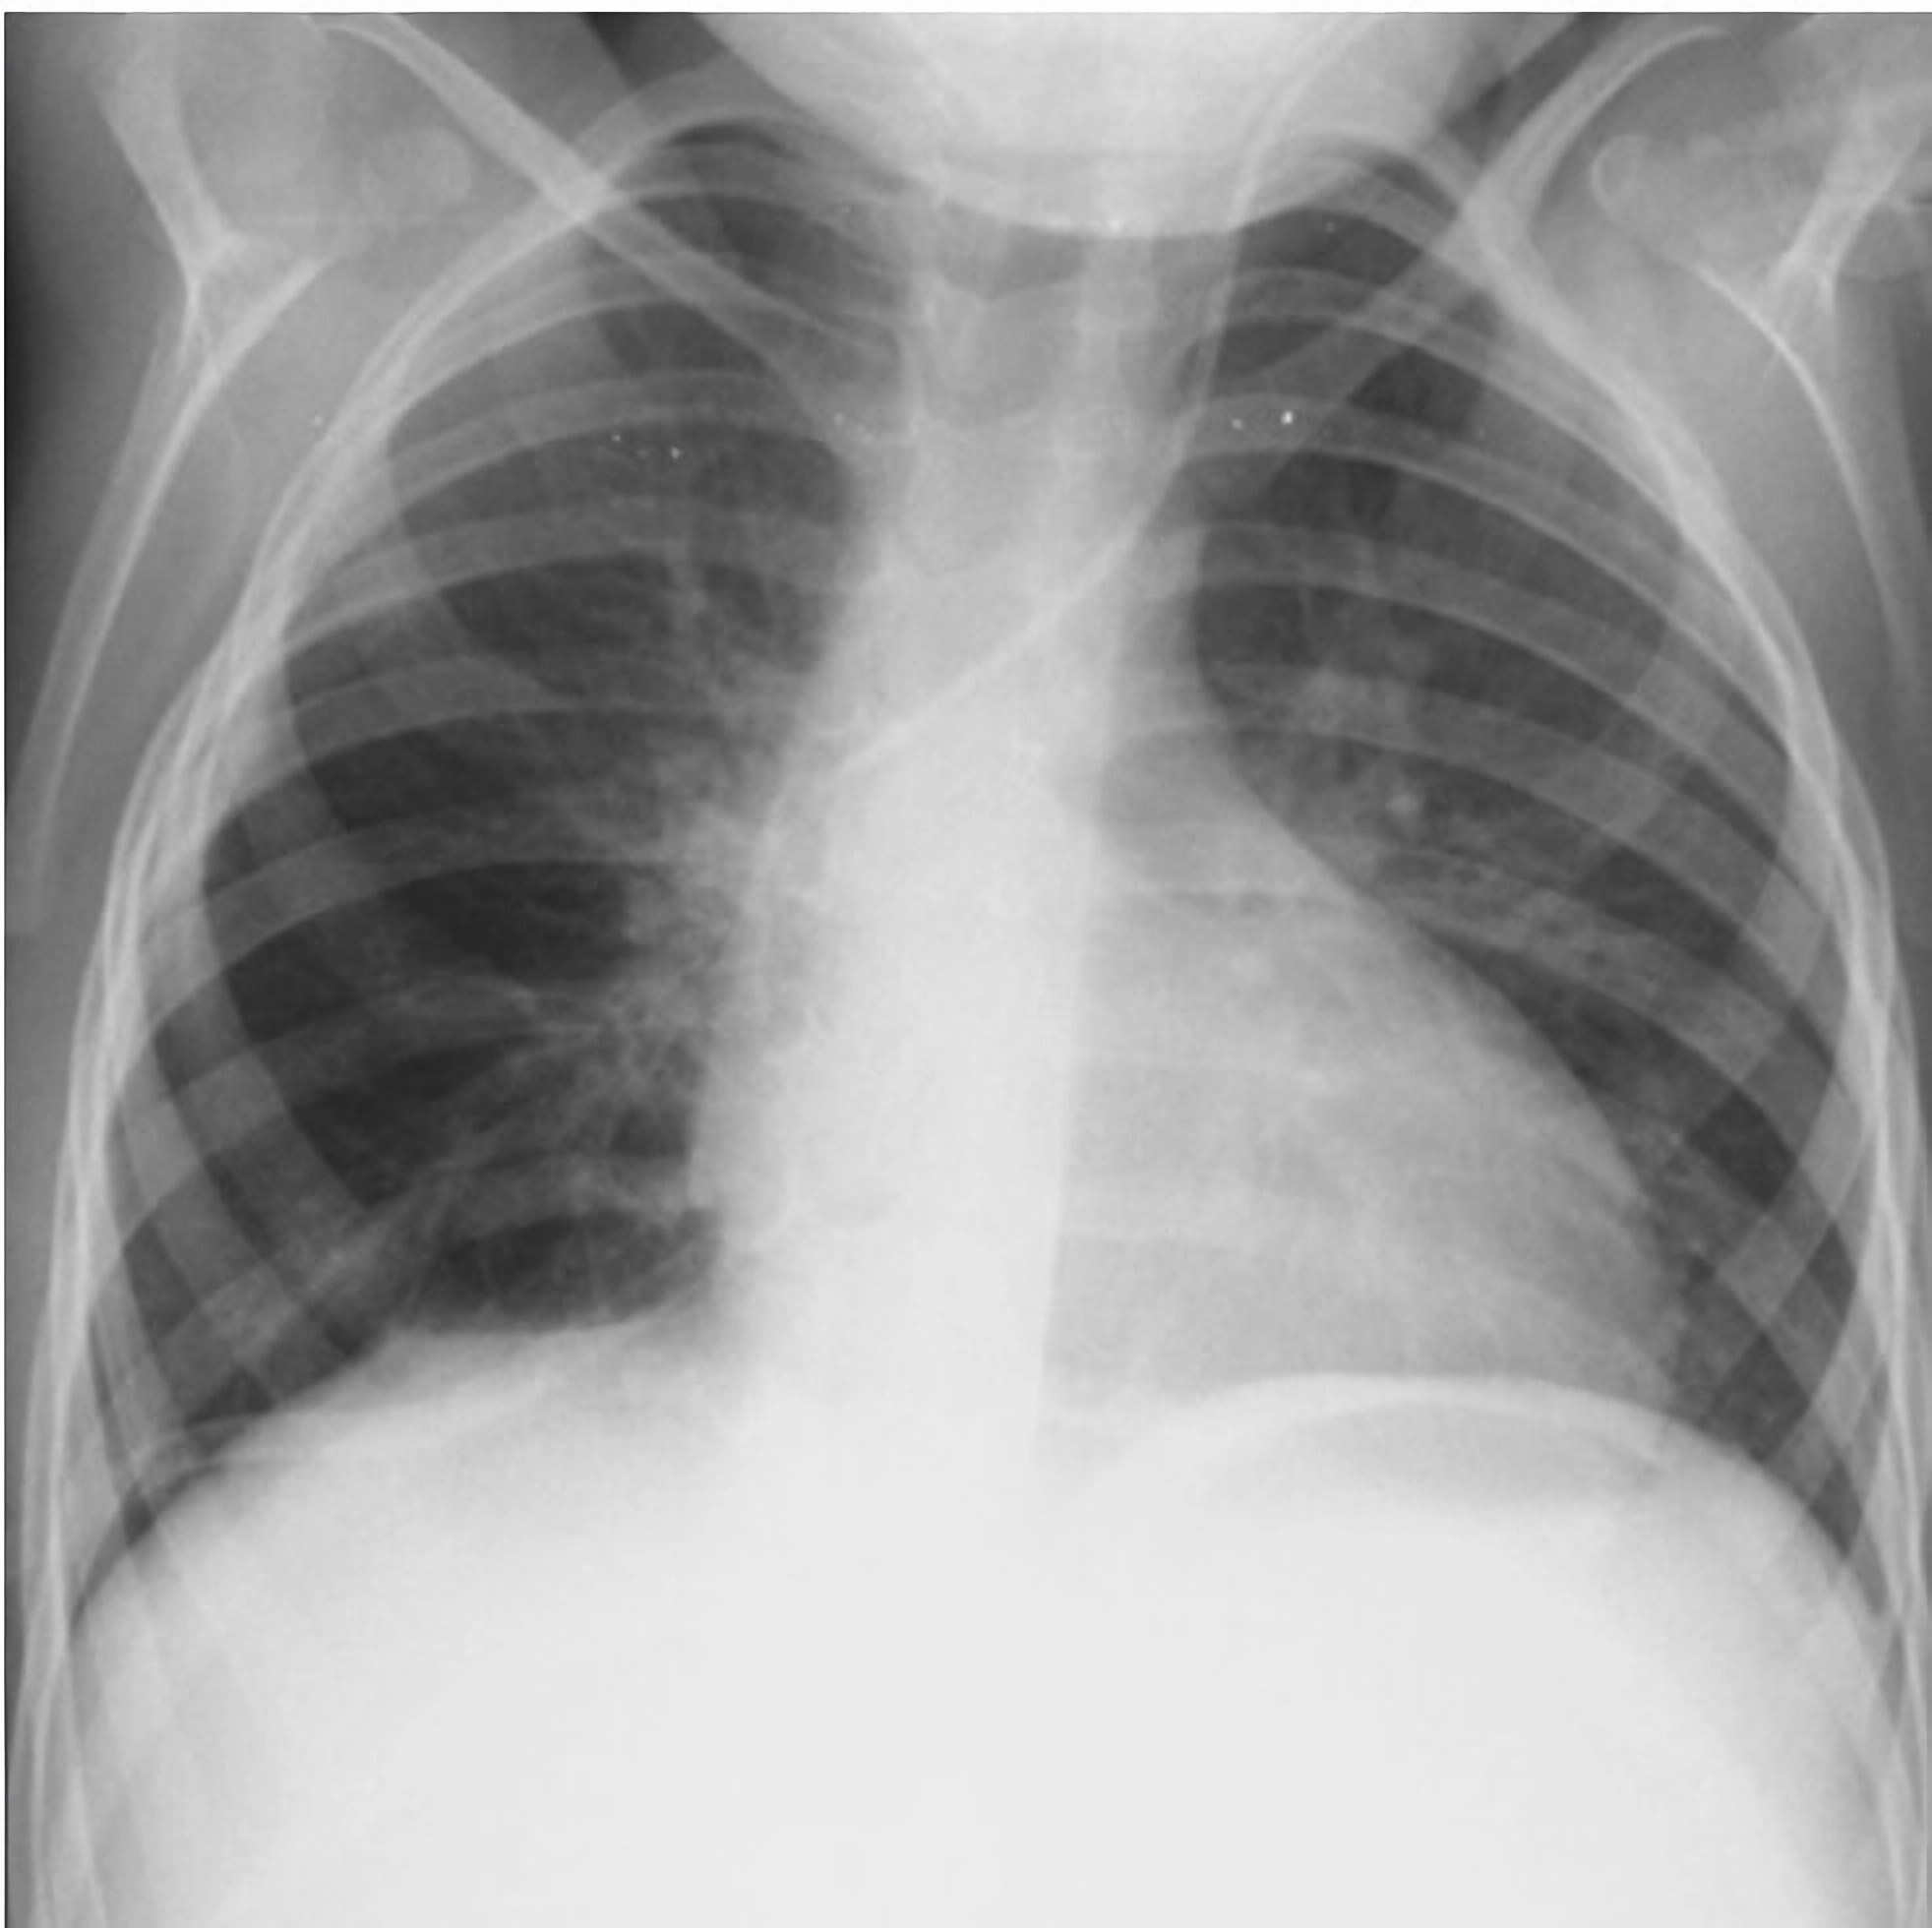

Evoluția postoperatorie a fost favorabilă. Pacienta a fost extubată în prima zi după intervenție, iar radiografia toracică efectuată în ziua a doua postoperator a confirmat reexpansiunea completă a plămânului drept, fără semne de revărsat pleural. Tubul de dren a fost suprimat după 48 de ore.